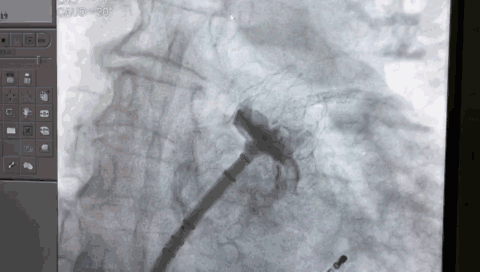

封堵伞展开后造影